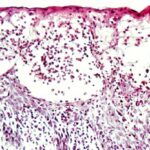

The vesicles seen during the first stage arise within the epidermis and are associated with spongiosis. They are of the type seen in dermatitis . However, they differ from the vesicles of dermatitis by the numerous eosinophils within them and around them in the epidermis (eosinophilic spongiosis) . The epidermis between the vesicles often shows single dyskeratotic cells and whorls of squamous cells with central keratinization. Like the epidermis, the dermis shows an infiltrate containing many eosinophils and some mononuclear cells.

The alterations in the second stage consist of acanthosis, irregular papillomatosis, and hyperkeratosis. Intraepidermal keratinization, consisting of whorls of keratinocytes and of scattered dyskeratotic cells, is often more pronounced than in the first stage. The basal cells show vacuolization and a decrease in their melanin content. The dermis shows a mild, chronic inflammatory infiltrate intermingled with melano-phages. This infiltrate extends into the epidermis in many places.

The areas of pigmentation seen in the third stage show extensive deposits of melanin within melanophages located in the upper dermis. Usually, this dermal hyperpigmentation is found in association with a diminution of pigment in the basal layer, the cells of which show vacuolization and degeneration . In some cases, however, the cells of the basal layer contain abundant amounts of melanin .